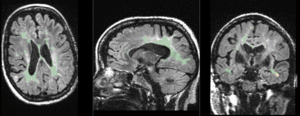

Registration Results

RegLib C02 unregistered.gif baseline & T2 before registration (click to enlarge)

RegLib C02 registered.gif baseline to T2 after affine+nonrigid alignment (click to enlarge)